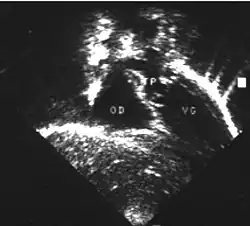

- Les coupes échographiques les plus utiles à cette fin sont :

- La coupe parasternale gauche grand axe : elle montre que le vaisseau issu du ventricule gauche (le plus postérieur) se dirige anormalement vers l'arrière et se bifurque précocement. C'est donc le tronc pulmonaire et non l'aorte comme normalement.

- Les coupes sous costales qui montrent bien le trajet parallèle des gros vaisseaux et leur inversion. Cet examen permettra d'éliminer en particulier un retour veineux pulmonaire anormal total bloqué qui aurait pu rendre compte de l’hypervascularisation pulmonaire sur la radiographie des poumons.